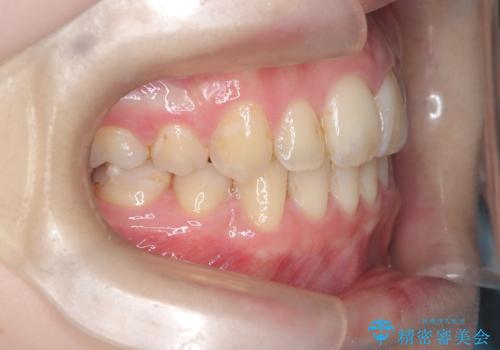

- 「歯のデコボコ、八重歯、口ボコが気になる」を主訴に来院された患者様です。

上下左右4番(4本)の歯を抜歯しワイヤー矯正で治療を行いました。

計4本の抜歯を行い、歯のデコボコと口元がすっきりし、大変ご満足していただけました。